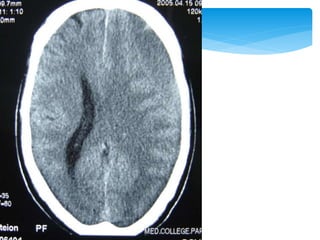

 Between thedura mater and inner table of the skull; usually in the temporal or temporoparietal region  Tearing of the middle meningeal artery or, less commonly, secondary to venous bleeding  Directly related to the status of the patient before surgery  Close to 0 for patients not in a coma, 9% for obtunded patients, and 20% for patients in deep coma Extradural Haematoma

 Between thedura mater and arachnoid membrane  Tearing of bridging veins  Severe brain damage more likely than with epidural haematomas  Approximately 60%, but can be lowered with rapid surgical intervention and aggressive medical management Subdural Haematomas